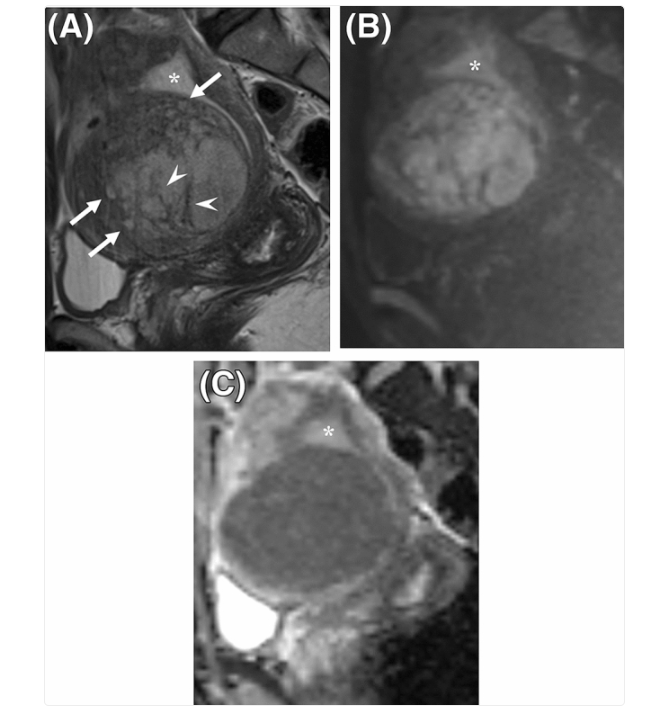

MRI helps doctors distinguish between different types of uterine tumours by showing their size, shape, and how they interact with nearby tissues.

This is a rare cancer of the muscle layer. This type shows up as a large, uneven mass that may contain spots of dead tissue (necrosis) and looks very mixed or “patchy” on scans27.

The most common non-cancerous growth, which shows up as a well-shaped, dark mass that doesn’t invade surrounding tissue28,30.